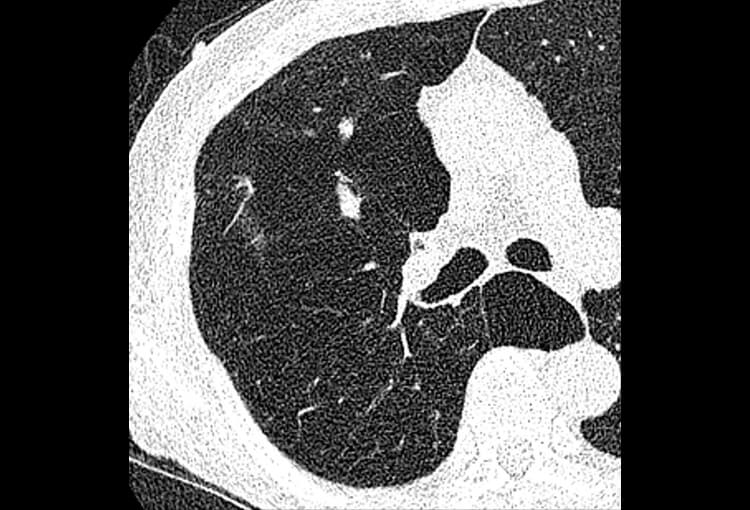

120 kV / 30 mAs / 1mm

Before FBP (Noise 150) VS After ClariCT.AI (Noise 49) 67% Denoising